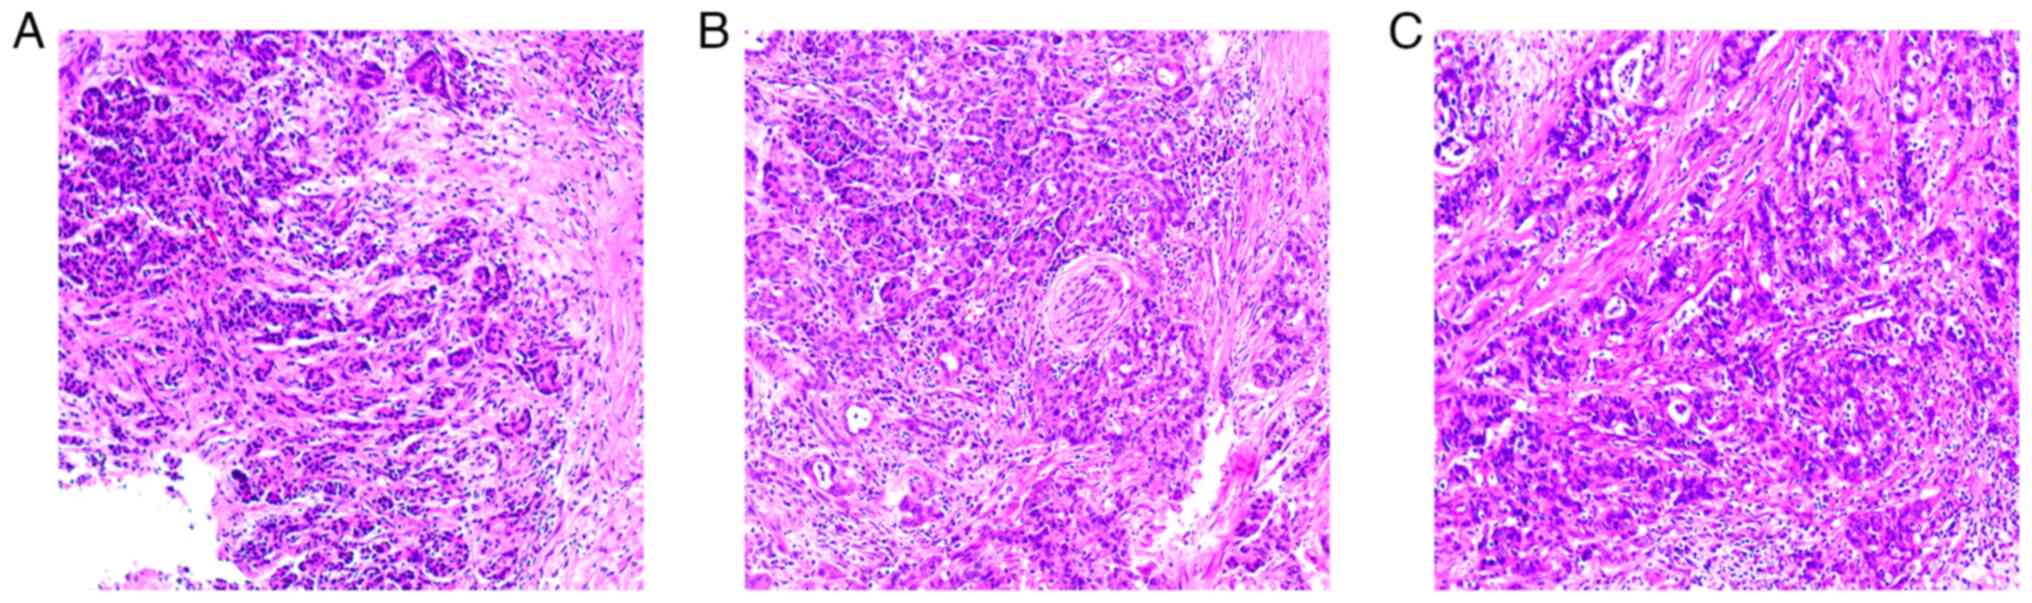

Figure 1

Hematoxylin and eosin staining revealed irregular cancerous glands arranged in a crowded and disorganized manner, infiltrating the pancreatic parenchyma. The nuclei of glandular epithelial cells appeared large and deeply stained, exhibiting obvious pleomorphism and undergoing visible nuclear fission. Additionally, there was a significant presence of peripheral mesenchymal fibroplasia, along with the observed invasion of vasculature and nerve structures. Images were obtained at (A and B) x100 and (C) x200 magnification.

A 68-year-old male with no family history presented to the First Affiliated Hospital of Nanchang University (Jiangxi, China) in August 2021, complaining of epigastric pain. An abdominal computed tomography (CT) showed a space-occupying lesion in the body of the pancreas. Enhanced CT scans of the chest and pelvis showed no abnormalities. Preoperative carbohydrate antigen 19-9 (CA199) levels were significantly elevated at 798.7 U/ml (normal range, 0-27 U/ml). Given the confined nature of the lesion and the absence of distant metastasis, proceeding with surgical intervention was deemed appropriate. Subsequently, the patient underwent laparoscopic radical pancreatic body-tail resection and splenectomy. The postoperative pathology confirmed a diagnosis of moderately differentiated ductal adenocarcinoma (pT3N0M0) (Fig. 1). The degrees of surgical resection in patients are mainly divided into three parts: Complete resection of the tumor (R0), microscopic residual (R1) and visual residual of the tumor (R2), respectively. The present study mainly adopted the presence or absence of tumor infiltration within 1 mm from the cutting edge as the criterion for judging the R0 or R1 resection of the tumor (17,18). Tumor cells are resected as R1 if they are found within 1 mm of the tip of the tissue; if no tumor cells are found, it is resected as R0. R2 indicates residual tumors visible at the surgical margins (positive margins). The patient in the present case had undergone laparoscopic radical pancreatic body-tail resection and splenectomy, which was considered a R0 resection in conjunction with the postoperative pathological results.